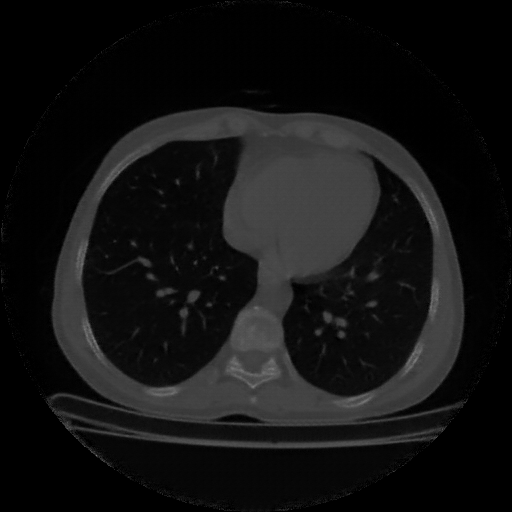

Original NATIVE CT scan (input)

Full window (WL 1023.5, WW 4095 β†’ Low βˆ’1024, High +3071)

Lung window (WL -600, WW 1500 β†’ Low βˆ’1350, High +150)

Mediastinum window (WL 40, WW 400 β†’ Low βˆ’160, High +240)